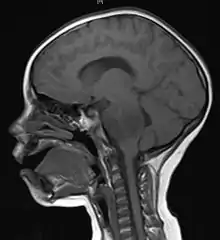

Imaging

Medical imaging plays a central role in the diagnosis of brain tumors. Early imaging methods – invasive and sometimes dangerous – such as pneumoencephalography and cerebral angiography have been abandoned in favor of non-invasive, high-resolution techniques, especially magnetic resonance imaging (MRI) and computed tomography (CT) scans,[38] though MRI is typically the reference standard used.[41] Neoplasms will often show as differently colored masses (also referred to as processes) in CT or MRI results.

More recently, advancements have been made to increase the utility of MRI in providing physiological data that can help to inform diagnosis and prognosis. MRI itself is sufficient in identifying the brain tumor’s location and morphology, but other types of MRI may be used on top of that, such as MRA, MRS, pMRI, fMRI, and DWI. These imaging techniques help doctors and surgeons to diagnose the type of tumor, to plan for surgery, and to assess treatment and radiation/chemotherapy.